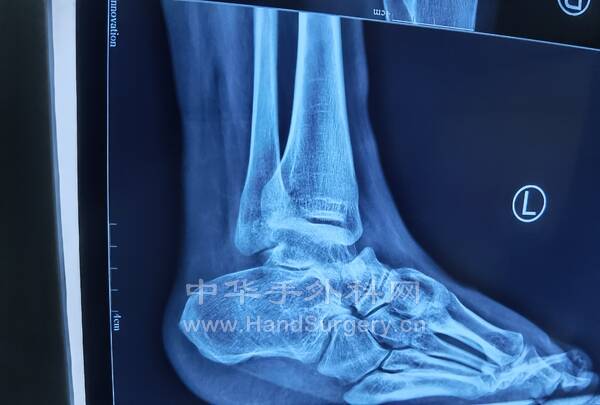

马蹄内翻足患者DR片:

双足正侧位(负重位),双踝正侧位(负重位),双下肢全长正位,双跟骨轴位

2.三代遗传的马蹄足患者,今日手术(见图),术式:经皮跟腱延长术,跖筋膜松解术,胫前肌腱1/2转位术,跟骨截骨外移术,第一跖骨上抬术,组合式外固定架固定术